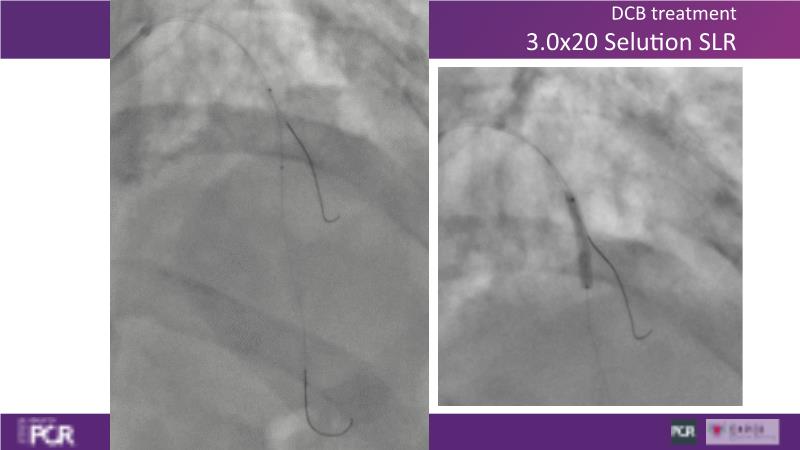

Through the study of two cases, this session examines the need for stenting bifurcation lesions and the role of DEB technology in avoiding stent-related complications in long diffuse disease. It emphasizes the benefits of SELUTION SLR balloons for de novo lesions, discussing how sustained limus release technology can broaden DEB indications and reduce metal usage, understanding the limitations of DES and the emerging role of DEB with sustained limus release, and learning how to identify dissections that can be left unstented.